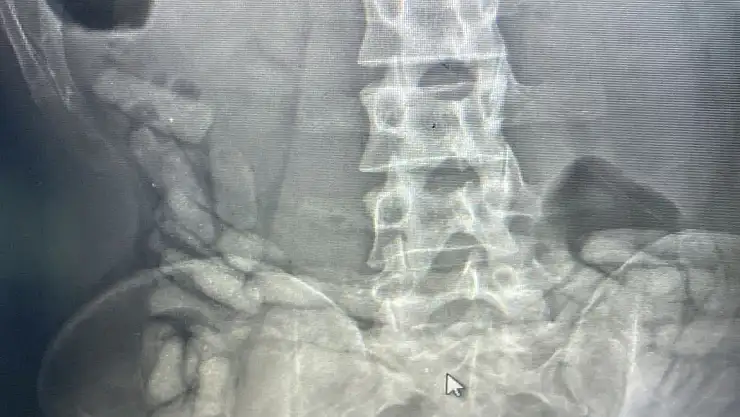

Ağrı'da İran uyruklu bir şahsın midesinden 55 kapsül halinde toplam 432 gram afyon sakızı ele geçirildi.

Ağrı Narkotik Suçlarla Mücadele Şube Müdürlüğünce uyuşturucu madde ticareti, kullanımı ve sokak satıcılarının faaliyetlerini önlemeye yönelik yapılan çalışmalar neticesinde yakalanan İran uyruklu A.G. isimli kişinin Doğubayazıt Devlet Hastanesinde yapılan iç beden muayenesinde, midesinde yabancı maddeler olduğu tespit edildi. A.G.’nin midesinden çıkarılan 55 kapsül halinde toplam 432 gram afyon sakızına el konuldu. Şahıs, "uyuşturucu veya uyarıcı madde ticareti yapma veya sağlama" suçundan sevk edildiği adli makamlarca tutuklandı.